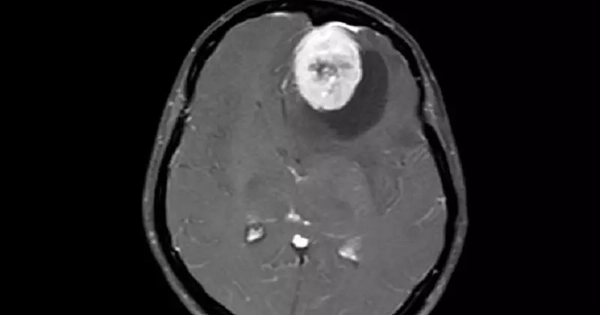

Người phụ nữ bị u màng não khổng lồ, bác sĩ chỉ ra những dấu hiệu dễ nhầm lẫn

Thường xuyên xuất hiện những cơn đau đầu và chóng mặt, nữ bệnh nhân cho rằng mình chỉ bị mệt mỏi do áp lực công việc kéo dài. Tuy nhiên, các triệu chứng không thuyên giảm mà ngày càng nặng hơn, âm thầm che giấu một khối u khổng lồ ở màng não suýt cướp đi tính mạng bệnh nhân.